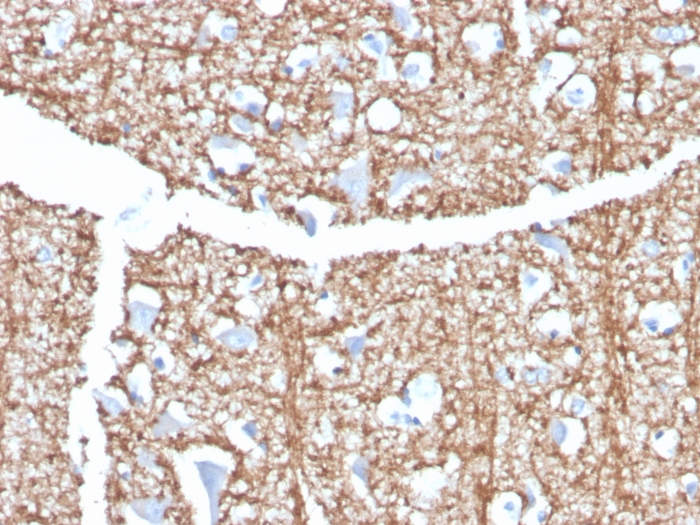

Formalin-fixed, paraffin-embedded human brain stained with Myelin Basic Protein Rat Monoclonal Antibody (MBP/4273).